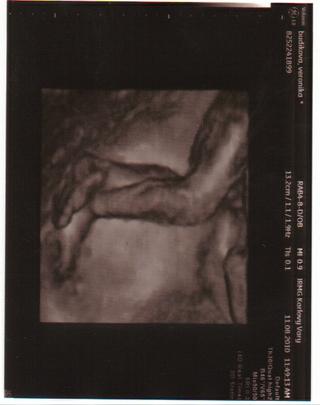

Ahoj holky, jsme tu jen na skok, hlásím, že dnešní UTZ po AMC v pořádku, vše jak má být, jen náš prcek se odmítal opět fotit - no aspoň se ne,ůže hádat komu je podobný. nechtěl nám ukázat obličej, schoval si ho ručkama a pro jistotu jej ještě zabořil do dělohy :-/ No sabotér. takže z 3D máme jen fotečku nožiček 😀 Malej jinak odpovídá jak má, i když dle měření je 22tt+6 a já jsem teprv jen 22+0 😅 No jsem ráda, že se mu u mě daří tak dobře 😀 😀